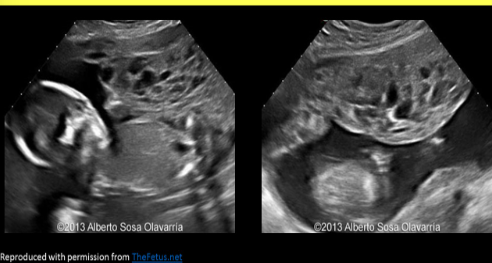

Partial mole

Fetus and molar pregnancy; can occur with an abnormal or normal fetus

If abnormal, most fetuses are triploid (2 sperm, 1 egg = 3 copies of all)

Area of heterogeneous molar tissue Adjacent to fetus

Placenta >4cm AP at 18-22 weeks

Partial molar pregnancy

Complete molar pregnancy